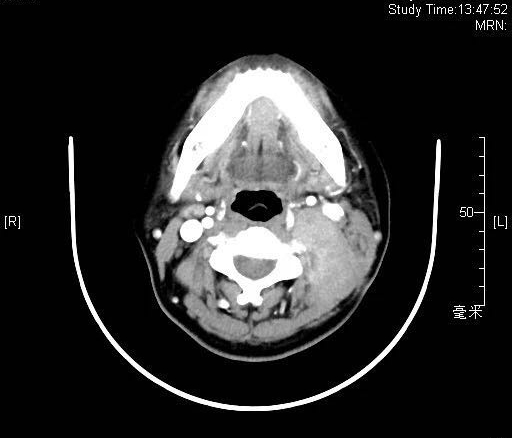

2018年8月患者入院时肿物约7*7cm大小

患者增强CT扫描显示,颈部肿物巨大,向前推压颈总动脉、颈内静脉,颈内静脉部分闭锁,向内侧侵及第1-3颈椎横突